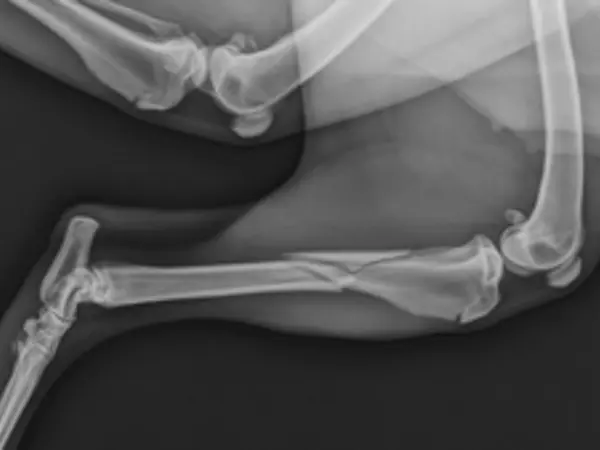

Vi har moderne udstyr til røntgen og ultralyd, som gør det muligt at undersøge både knogler, led, organer og blødt væv uden at belaste dit kæledyr unødigt. Røntgenundersøgelser anvendes ofte til at vurdere skader, ledproblemer eller sygdomme i bryst- og bughulen, mens ultralyd giver os mulighed for at se detaljerede billeder af indre organer og bløddele.